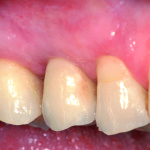

Estetica e tessuti molli in implantologia

Stefano Volpe

Clinica Feltre/Fiera di Primiero Implant Research Group

Riassunto

Gli obiettivi estetici dell’odontoiatria implantare dovrebbero essere simili a quelli della protesi convenzionale. Nelle riabilitazioni implanto-protesiche nei settori anteriori la...